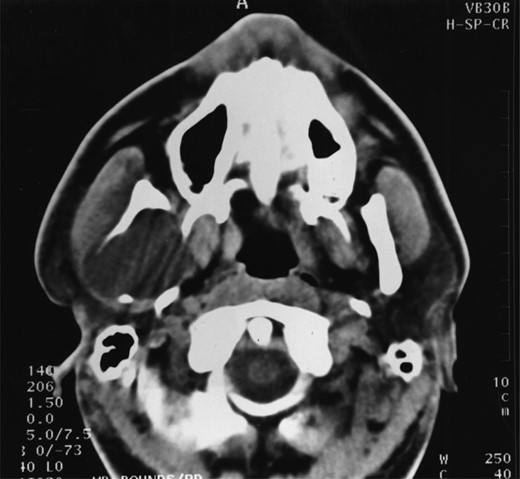

A 25-year-old man presented with a 2-month history of facial pain and limited mouth opening associated with a 3-week history of swelling of the right cheek. Radiographic analysis revealed a loculated, fluid-filled, well-demarcated lesion destroying and expanding the ascending ramus, extending out into the soft tissues, from the condyle down to the angle (Fig. 1).

A well-demarcated lesion extending out into the soft tissues from the ramus of the mandible.